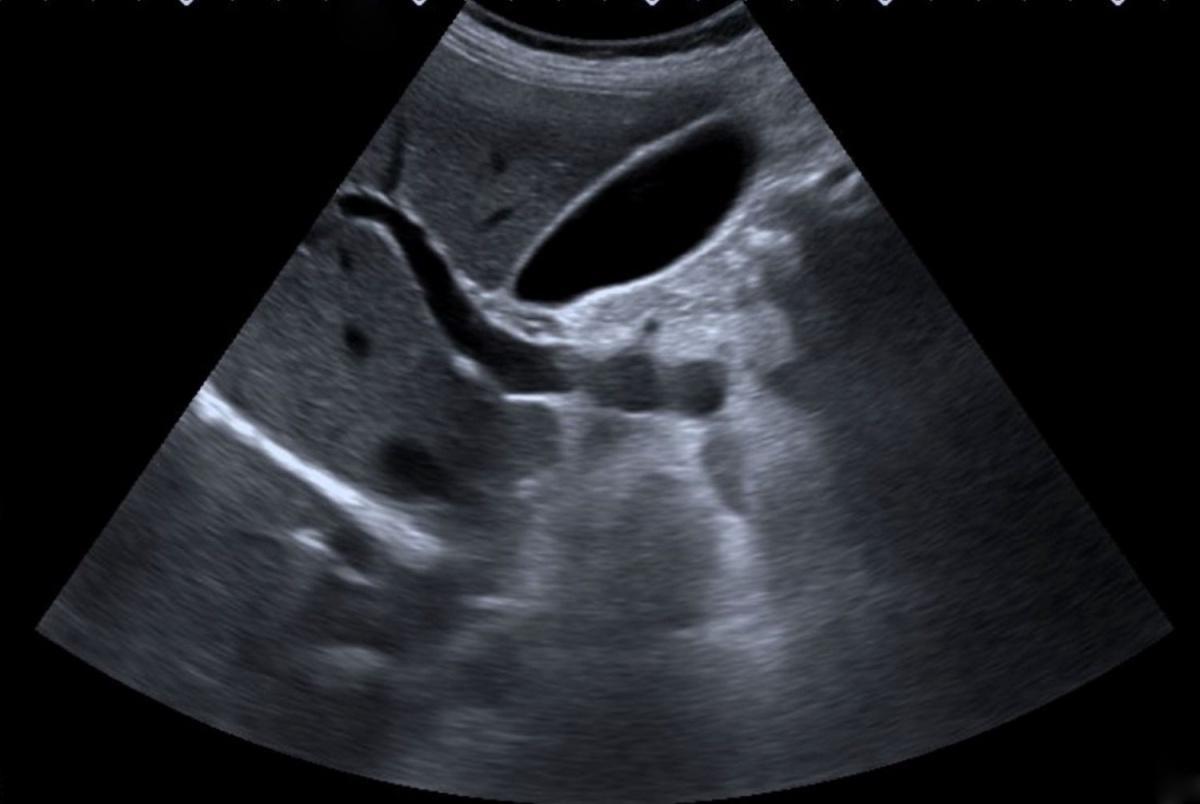

RAJAAISYA/SCIENCE PHOTO LIBRARY / Getty Image

💧 La Vésicule Biliaire — Repérage et Aspect Normal

La vésicule biliaire se situe sous le lobe hépatique droit, souvent dans le plan sagittal médian.

Elle se repère facilement grâce à la veine porte principale, que l’on suit depuis le pédicule hépatique jusqu’à son entrée dans le hile.

L’aspect normal est celui d’une structure allongée, anéchogène, à paroi fine (≤ 3 mm), avec un contenu clair, sans écho interne.

🔹 Lithiase Vésiculaire

Les calculs apparaissent comme des structures hyperéchogènes mobiles avec cône d’ombre postérieur.

Ils bougent avec le changement de position du patient (test de mobilité).

Un calcul enclavé dans le col ou l’infundibulum (calcul impacté) est un signe majeur de cholécystite.